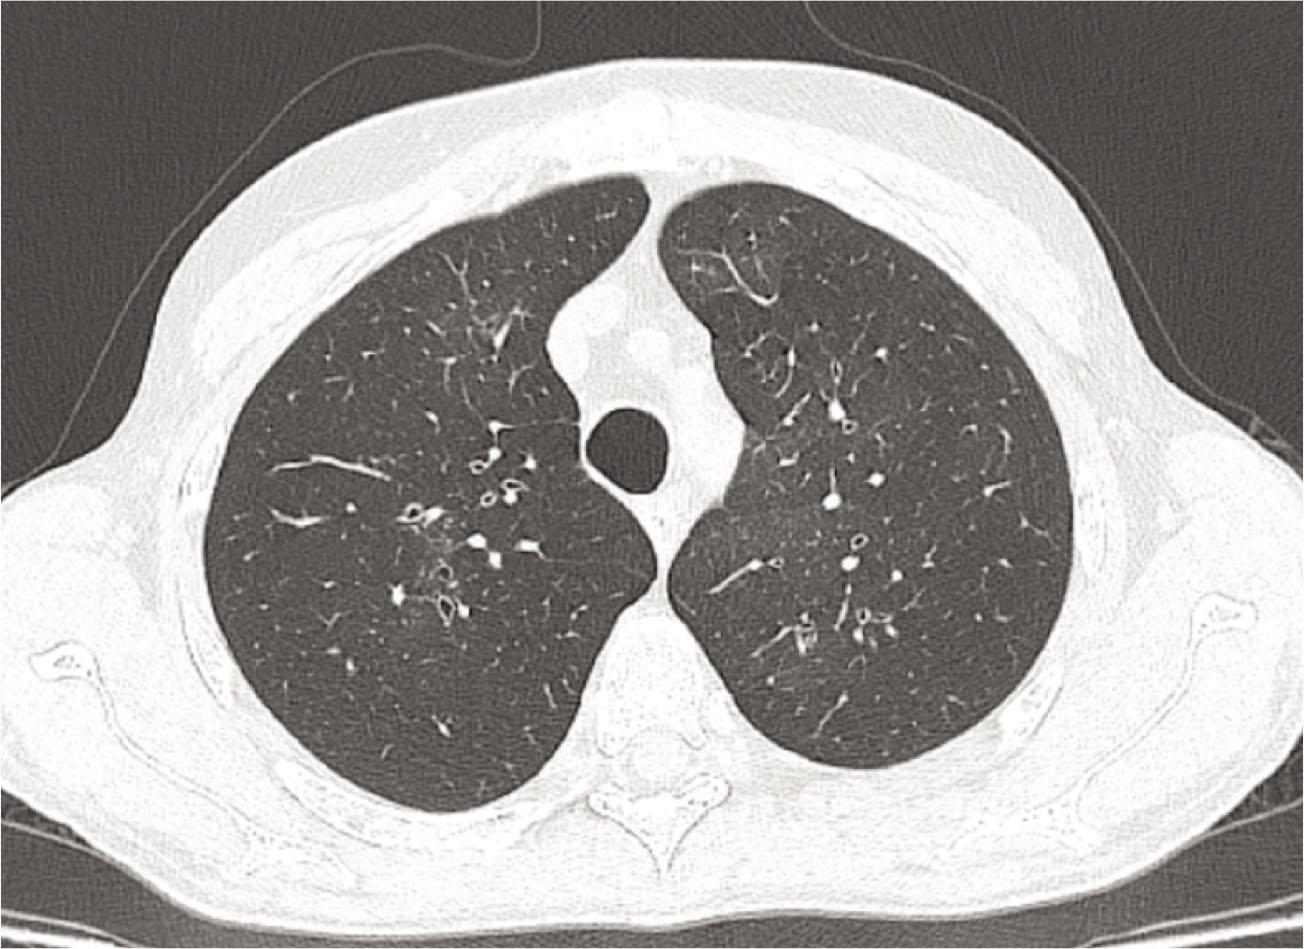

Figure 2.

| HR–CT | Mosaic attenuation | Mosaic attenuation | Increased lucency, predominantly in the basal regions |